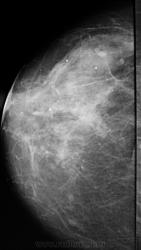

- https://radiomed.ru/sites/default/files/styles/case_slider_image/public/user/1787/P1010697.JPG?itok=O-mbU0IA

На фоне фиброзной мастопатии определяются с обеих сторон рассеянные микрокальцинаты и мелкие стромальные, а справа в в/н квадранте подозрительные сгруппированные - нужна пункция